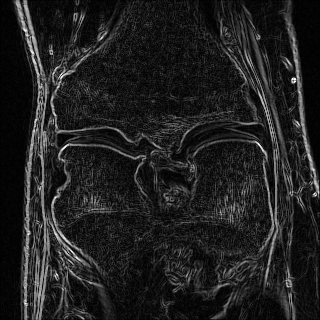

Edge preserving has always been a crucial concern in the design of reconstruction models. To improve the quality of reconstructed images and preserve image edges, some works suggested introducing edge priors in the original restoration problem to preserve image edges [4, 34]. However, they will suffer from complicated algorithm design and time-consuming training processes. Recently, some more efficient methods have been proposed to use edge maps as external guidance for image restoration. For example, Yang et al. [48] used off-the-shelf edge detectors to extract image edges from the degraded images. Fang et al. [12] predicted image edges by constructing an edge reconstruction network. Huang et al. [18] designed a novel dual discriminator GAN framework for solving fast multi-channel MRI, in which one GAN network is built for edge information enhancement. Inspired by these methods, we also consider introducing image edge prior as external guidance to MRI reconstruction since 1) image edges are prominent and distinguishable features in MRI (see Fig. 1), which can serve as a good guide to the model to recover high-frequency details; 2) the ground truth edges can be easily fetched via ordinary edge extraction operators, like Canny, Sobel, and Prewitt, which means that the edge maps can be learned in a data-driven manner. However, how to effectively utilize image edge priors to guide image reconstruction still remains a challenge. In some methods, edge information was simply concatenated with the input image and passed to the next stages. Though this is a simple way to utilize the edge priors, it may not give full play to the guiding role of the edge priors. Therefore, in this work, we want to explore a more efficient and effective mechanism to fully take advantage of image edge priors.

(a)

(b)

(c)

fastMRI is a large-scale MR dataset jointly established by Facebook AI Research and NYU Langone Health. It provides both knee and brain datasets for evaluation. In our work, we use the multi-coil knee dataset, which was acquired on three clinical 3T systems or one clinical 1.5T system using a 15-channel knee coil array. The dataset includes data from two pulse sequences, yielding coronal proton-density weighting with (PDFS) and without (PD) fat suppression. As is shown in Fig. 1, PD images usually contain more structural and prominent edge features than PDFS images, which suggests that it is more challenging to use edge guidance on PDFS datasets. Therefore, we explore the effectiveness of EAMRI on these two modalities. Following [13], for both PD and PDFS knee datasets, we separately filter out 227 volumes (8332 slices) for training and 24 volumes (1665 slices) for testing. The dataset is centrally cropped to .